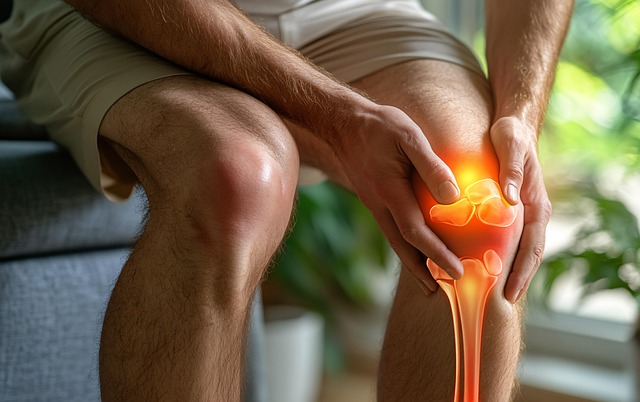

2. 관절과 무릎 통증 완화

복용 후 무릎의 뻣뻣함, 통증이 줄어들었다는 체감 후기가 다수입니다. 특히 아침 기상 직후 관절이 더 부드러워졌다는 경험담이 많습니다. 단순 통증 억제가 아닌, 뼈 자체를 강화함으로써 일상 속 불편을 줄여준다는 점에서 만족도가 높습니다.